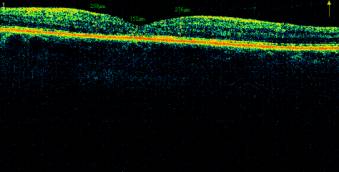

Illustration 5. The fundus and OCT macular

patient M., 52g. PPDR with DHS to resolve after combined treatment and LC.